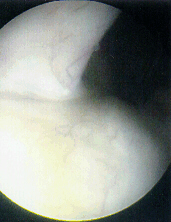

Meniscal Repair

- Collagen healing is possible in capsular third of meniscus- area where

most meniscal injuries occur in children

- Repairing tear in young individuals when technically feasible is prudent

when considering the natural history of alternative treatments